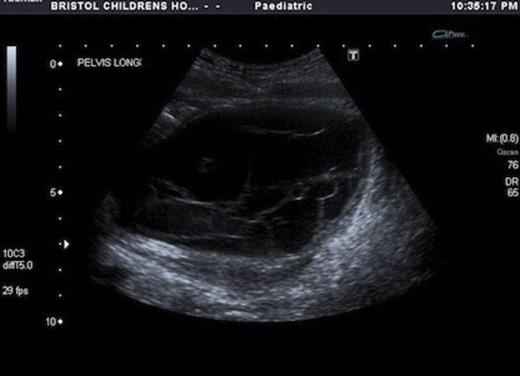

USS showed a septated cystic structure behind the bladder and abutting the ovary. There was echogenic fluid within the cysts. (Fig 1&2)

Accurate preoperative diagnosis can be difficult. Ultrasound has been used as the first line for diagnosis. It shows a wide range of findings (8), but the majority are simple cysts. Multilocular cysts, as in our case are very rare accounting for only 4% of the cases (8). Occasionally a normal ovary abutting a cyst gives a clue to the origin of these cysts but accurate pre op diagnosis remains rare.